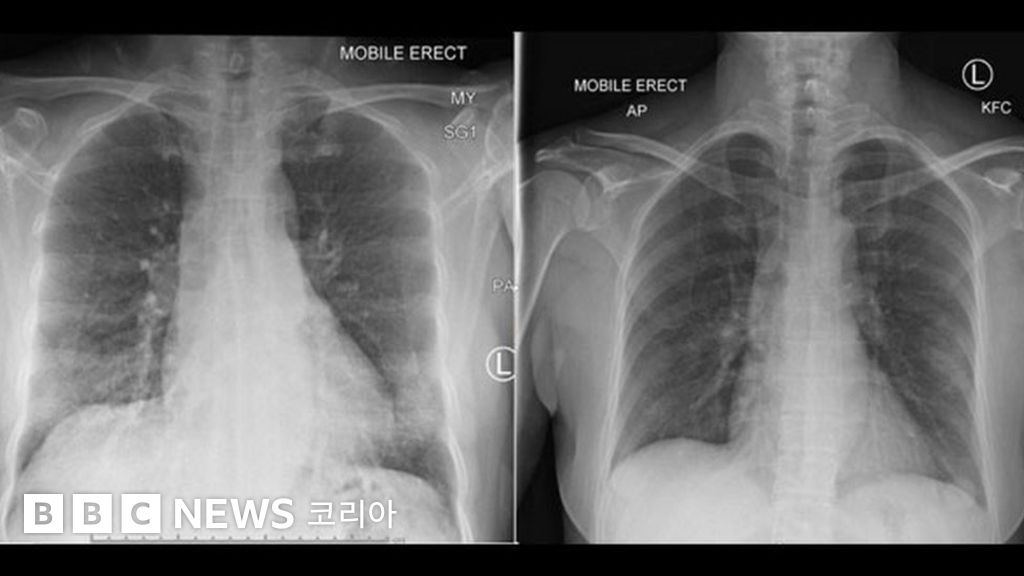

사진 출처, PETER DOHERTY INSTITUTE